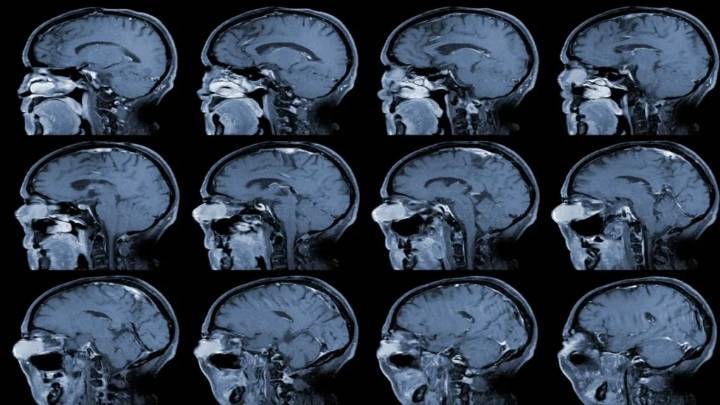

Recientemente la socialité, modelo y empresaria Kim Kardashian, reveló por medio del reality The Kardashians un problema médico que se le diagnosticó por medio de una resonancia magnética, el cual se trata de un aneurisma cerebral, mismo causado por el estrés que ha presentado con problemas personales.

Un aneurisma cerebral se forma cuando una arteria del cerebro se debilita y se infla, creando una pequeña bols